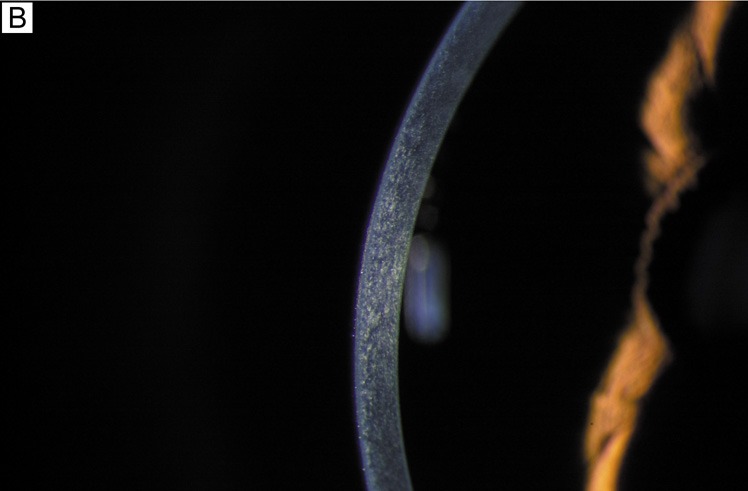

Fig. 1. (A) Diffuse illumination slit-lamp view of the human cornea. (B) Slit-beam illumination slit-lamp view of the human cornea shows an optical section of the tissue. Notice the slight light scattering that occurs in the tissue, mainly from cellular components in cornea. (C) Histologic diagram of the major cellular and extracellular matrix components of the human cornea (toluidine blue 25×).

The cornea covers the anterior one-sixth of the total circumference of the globe (Fig. 1), whereas the sclera covers the remaining five-sixths. The cornea is a clear, transparent, colorless avascular structure richly supplied with sensory nerve endings that generally subserve touch and pain. There are no lymph vessels or other channels for bulk fluid flow. The interface between the corneal tear film and the ambient atmosphere provides roughly two-thirds of the refractive power of the human eye. The cornea itself is resilient, yet is described as viscoelastic in its response to stretching forces.